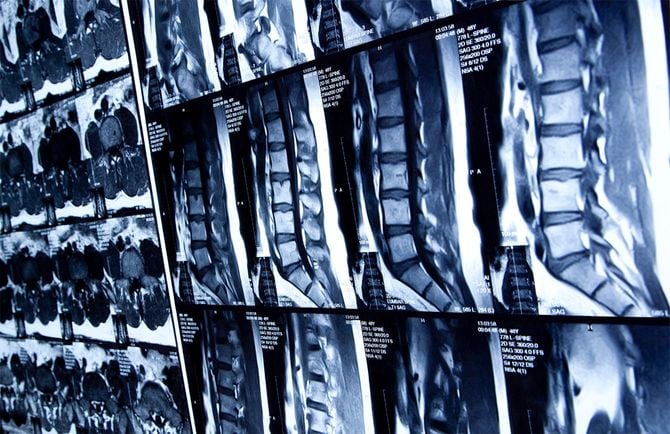

一方、夫の腰は深刻だった。さまざまな検査の結果を踏まえ、整形外科の医師から、圧迫骨折、脊柱管狭窄症、骨粗鬆症と診断されるが、「悪い病気の可能性がある」ことから、さらに詳しく検査をしていくことに。

夫の腰椎の一部はバラバラに砕け、空洞状態になっていた。

主治医となった医師は、知多さん夫婦に「多発性骨髄腫」と告げた。「多発性骨髄腫」とは、病気が進行すると骨の破壊による痛みや骨折、腎障害、また造血が妨げられることによる貧血、感染症など、さまざまな症状や臓器障害が現れるようになる“血液のがん”だった。